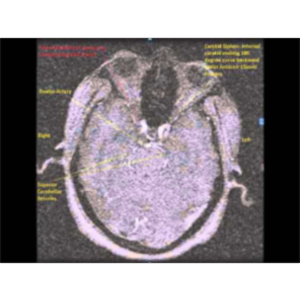

Demonstration of Vertebro-Basilar Circulation and all relevant VB Stroke syndromes on a formalinized specimen of Human brain

Commentator is Dr Sanjoy Sanyal, Professor and Course Director of Neuroscience and FCM-III Neurology in the Caribbean. C